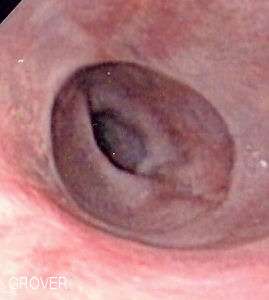

| Endoscopic image of Schatzki ring, seen in the esophagus with the gastro-esophageal junction in the background. | |

A Schatzki ring is usually diagnosed by esophagogastroduodenoscopy or barium swallow. Endoscopy usually shows a ring within the lumen of the esophagus which can be of variable size (see picture). The ring is usually located a few centimetres above the gastro-esophageal junction, where the esophagus joins the stomach. Schatzki rings can often resemble a related entity called an esophageal web. Esophageal webs also contain extra mucosal tissue, but do not completely encircle the esophagus.